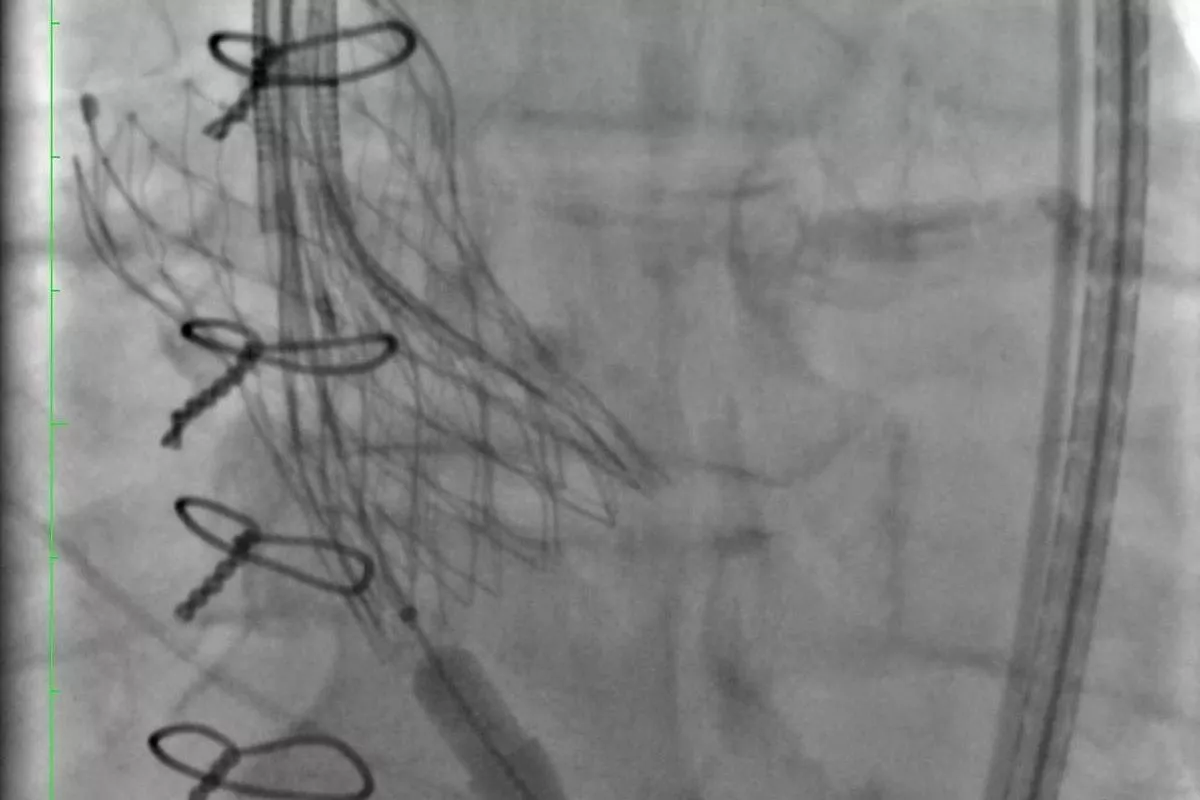

Врачи НИИ-Краевой клинической больницы №1 (НИИ-ККБ №1) много лет проводят операции по транскатетерной имплантации аортального клапана. Их делают через прокол в ноге, без наркоза. Но у протеза ограниченный срок службы – 10 лет. Потом он обрастает кальцием, и пациенту вновь нужна операция.

– Когда старый клапан уже износился, в этот же протез клапана ставится новый – методика «клапан-в-клапан» или по-простому говоря – по типу «матрешки». Недавно мы провели первую подобную операцию 70-летнему мужчине, вставив в старый изношенный протез аортального клапана новый клапан, – рассказал завотделением рентгенхирургических методов диагностики и лечения НИИ-ККБ №1 Алексей Федорченко.

Операция проводится малоинвазивным методом, что сокращает время реабилитации пациента и позволяет ему уже спустя пару дней вернуться к привычному распорядку жизни. Так, пенсионер скоро займется любимым хобби – рыбалкой.